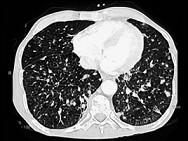

女,56岁,乳腺癌手术后,未行化疗,结合CT图像,选择最可能的诊断是 ( )A.肺转移癌B.肺结核C.间质性肺炎D.肺结节病E.肺曲菌病

问题 女,56岁,乳腺癌手术后,未行化疗,结合CT图像,选择最可能的诊断是 ( )

选项 A.肺转移癌 B.肺结核 C.间质性肺炎 D.肺结节病 E.肺曲菌病

答案 A